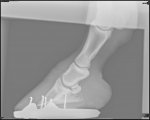

Xrays show there is a small amount of rotation in the left fore. Right fore is fine. I don’t have them on email yet but will share them when I do.

It’s minimal in the LF and vet hopeful it can be corrected with trimming and shoeing etc. Her toe on the LF is much longer than the RF so the rotation might even be less than it looks once the toe corrected. Sole depth looks good.

Xrays attached. You can see that one has some rotation and much more toe-that’s the one she was lame on.